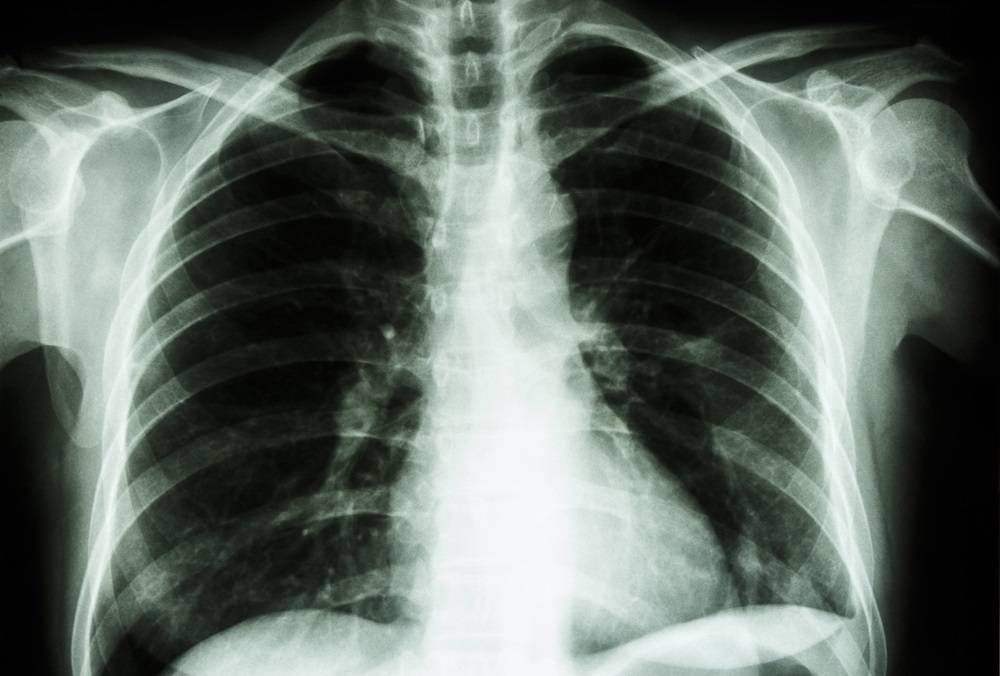

Medic pneumolog: așa arată plămânii afectaţi de COVID în proporţie de 80%. Ce trebuie să facem pentru a ne recupera?

Ceea ce știm de la începutul pandemiei este că infecția cu SARS-CoV-2 afectează plămânii. Cu acest prilej, medicul pneumolog...

Doctorul Alina Stanca: cum afectează coronavirusul plămânul

COVID-19 este o boală respiratorie, care ajunge în special în tractul respirator, care include plămânii.

COVID-19 poate provoca o serie...

Studiu alarmant. COVID-19 poate deteriora plămânii atât de grav încât „singura speranță” este transplantul

Tot mai mulți oameni de știință...

Cum distruge plămânul Covid-19. Experții ne explică pe larg procesul

Cum distruge plămânul Covid-19. Cercetătorii au găsit un posibil motiv pentru care unii pacienți cu Covid-19 suferă simptome de...